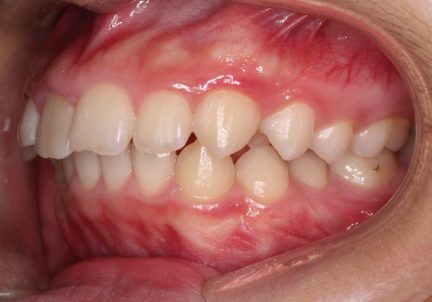

Classe II div 1, surplomb accru, rétrognathie mandibulaire, articulation profonde, arcades étroites, arcades asymétriques, déviation de la ligne médiane mandibulaire, décalage de la ligne médiane, chevauchement

- Relation de Classe I obtenue

- Guidage fonctionnel des canines des deux côtés

- Surplomb et recouvrement normaux obtenus

État initial

État final